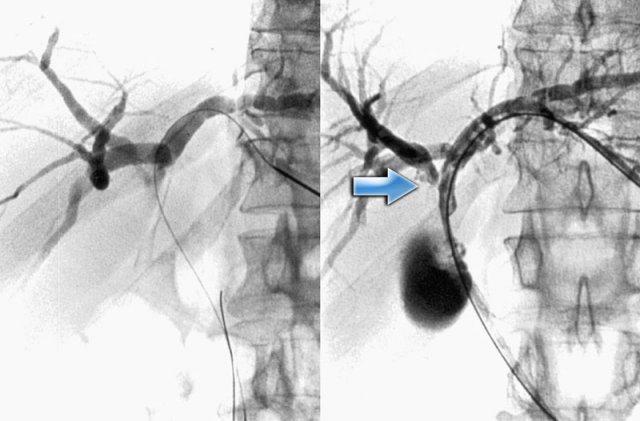

1. Introduction to Klatskin Tumor 1.1 Definition and Characteristics Klatskin tumor is a specific type of cholangiocarcinoma that develops at…

1. Understanding Bile Duct Cancer Bile duct cancer (cholangiocarcinoma) can develop in both intrahepatic (within the liver) and extrahepatic (outside…

1. Introduction to Bile Duct Cancer Bile duct cancer is classified based on its location: This cancer may grow slowly…

1. Introduction to Bile Duct Cancer (Cholangiocarcinoma) Bile duct cancer refers to a group of cancers that originate in the…